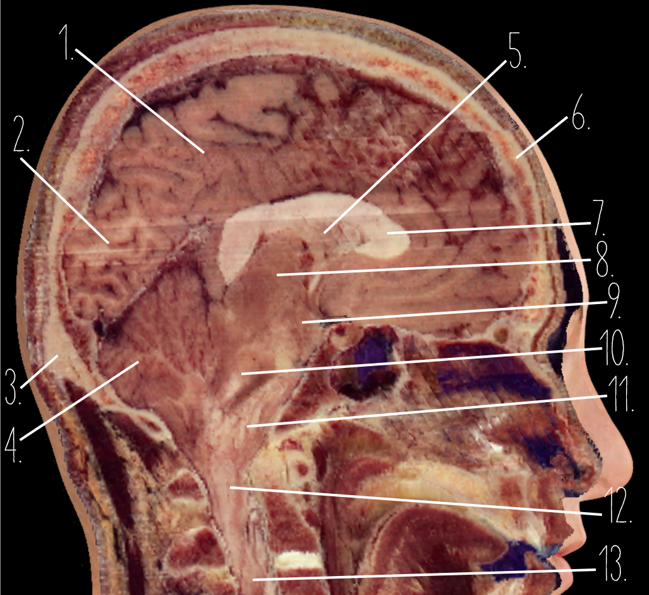

Brain Cross Sectional

127 Terms

1

Frontal Bone

2

Frontal Lobe

3?

Falx Cerebri

4?

Gray Matter

5?

White Matter

6?

Sulcus

7?

Gyrus

8?

Fissure

1?

Parietal Lobe

2?

Cerebellum

3?

Occipital Bone

4?

Cerebellum

5?

Lateral Ventricle

6?

Frontal Bone

7?

Corpus Callosum

8?

Thalamus

9?

Hypothalamus

10?

Midbrain

11?

Pons

12?

Medulla Oblongata

13?

Spinal Cord